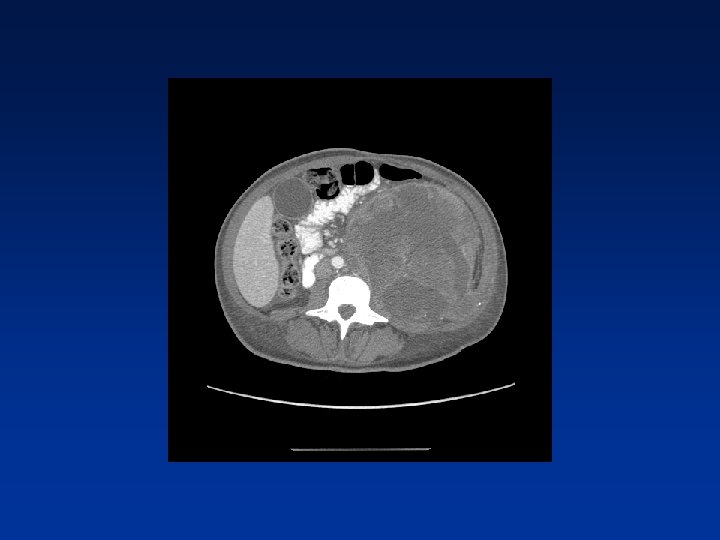

CASE